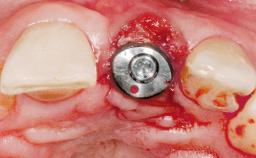

A 42-year-old female patient was referred to our clinic at the School of Dentistry of the University of São Paulo in November 2004, presenting a deficient restoration in the upper left central incisor. The clinical examination revealed no gingival retraction or any signs of gingival inflammation and, therefore, previous periodontal treatment was not considered. The patient presented a high lip line at full smile and a thin tissue biotype. This combination characterized a high-risk situation from an anatomic point of view, which required careful preoperative planning and cautious surgical execution.